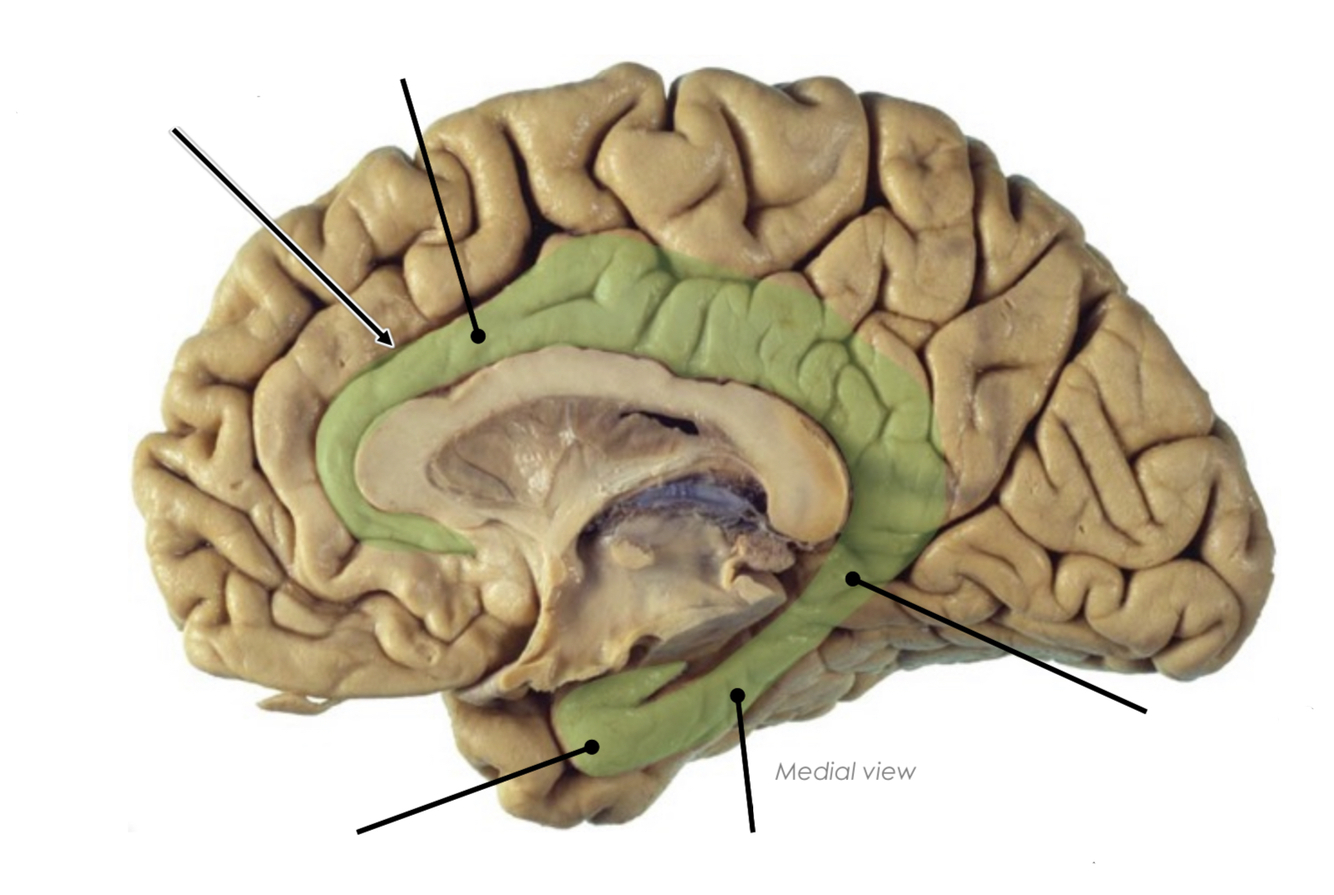

What are the following structures?

What is the isthmus?

A narrowing of the cingulate gyrus where it is continuous with the parahippocampal gyrus

What is the uncus?

The parahippocampal gyrus hooks upon itself anteriorly to form a bump called the uncus

Where is the cingulate gyrus located?

Below the cingulate sulcus and above the corpus callosum

What is the cingulum?

The cingulum is underlying the cingulate gyrus

it receives information from pre-frontal, parietal, occipital and temporal gyri

it is involved in the formation of memories and emotions

What kind of subcortical white matter fibre type is the cingulum?

Association fibres

these white matter fibres interconnect regions of one hemisphere with the limbic lobe and the hippocampus

Where is the cingulum?

What are the landmarks of the limbic system?

Landmarks are the bumpy regions we can see in the brain as they have something underneath them

the cingulum is a bundle of association fibres bringing information from the cortex and towards the limbic system